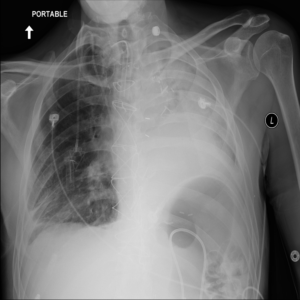

Anomaly detection is the problem of recognizing abnormal inputs based on the seen examples of normal data. Despite recent advances of deep learning in recognizing image anomalies, these methods still prove incapable of handling complex medical images, such as barely visible abnormalities in chest X-rays and metastases in lymph nodes. To address this problem, we introduce a new powerful method of image anomaly detection. It relies on the classical autoencoder approach with a re-designed training pipeline to handle high-resolution, complex images and a robust way of computing an image abnormality score. We revisit the very problem statement of fully unsupervised anomaly detection, where no abnormal examples at all are provided during the model setup. We propose to relax this unrealistic assumption by using a very small number of anomalies of confined variability merely to initiate the search of hyperparameters of the model. We evaluate our solution on natural image datasets with a known benchmark, as well as on two medical datasets containing radiology and digital pathology images. The proposed approach suggests a new strong baseline for image anomaly detection and outperforms state-of-the-art approaches in complex medical image analysis tasks.

翻译:异常检测是根据正常数据实例识别异常输入的问题。尽管在识别图像异常方面最近取得了深层次学习的进展,但这些方法仍然证明无法处理复杂的医学图像,如胸部X光几乎看不到异常和淋巴节点转移等。为了解决这一问题,我们引入了一种新的强有力的图像异常检测方法。它依靠古典的自动解剖器方法,经过重新设计的培训管道来处理高分辨率、复杂图像和图像异常分数。我们重新审视了完全不受监督的异常点检测的非常问题说明,在模型设置期间,根本没有提供异常的例子。我们提议放松这一不现实的假设,仅使用少量有限的异常点来开始搜索模型的超参数。我们评估我们使用已知基准的天然图像数据集以及包含放射学和数字病理图像的两个医疗数据集的解决方案。拟议方法为在复杂的医学图像分析任务中,为图像异常点检测和超常规状态方法提供了新的强基线。